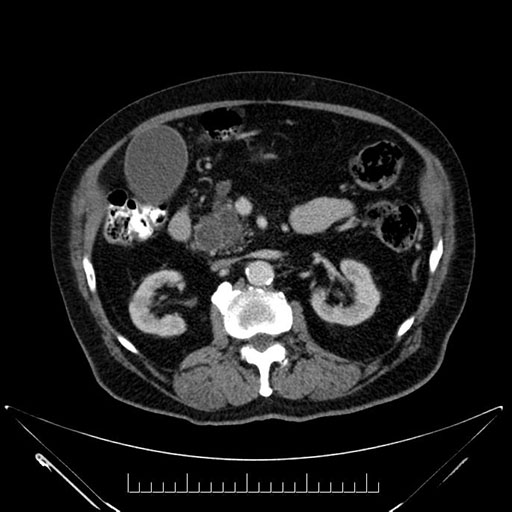

Axial - stented